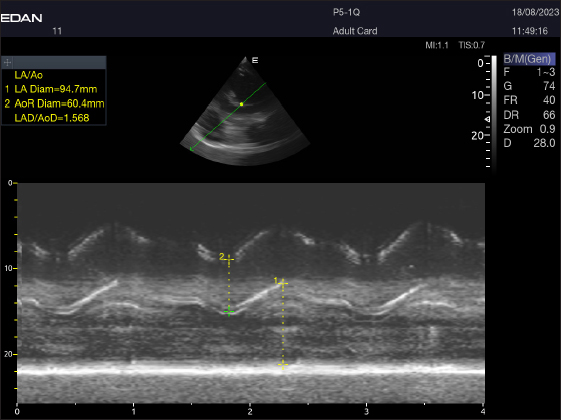

Fig. 4. LA/Ao ratios for the right parasternal short axis of 18 racing camels at the great vessel level. Through the anatomical M mode.

By positioning the probe perpendicularly in the fourth intercostal space or longitudinally in the fifth space with a little clockwise rotation, the interventricular septum, ventricles, and atria could be observed in the caudal long-axis four-chamber view (Fig. 1). From this vantage point, all camels could be seen to have a left ventricle, mitral valve, interventricular septum, right ventricle, and tricuspid valve. Figure 2 shows that in the short-axis image of the cardiac ventricles obtained with a little clockwise rotation at the 4th ICS, only the right ventricle, interventricular septum, and left ventricle were visible. Here, the dimensions of all camel heart were measured in M mode. The right parasternal two-dimensional short-axis pictures of the heart’s base in the first frame were used to determine the LA/Ao ratio, by applying 2D and M mode (Figs. 3 and 4). Despite some difficulties, we successfully acquired a pulmonary image by attempting to acquire the right ventricular outflow tract for the right short axis at the level of the great vessels.

Fig. 3. Right parasternal short-axis view of 16 she-camel at great vessel level showing Ao=aorta and LA=left atrium.